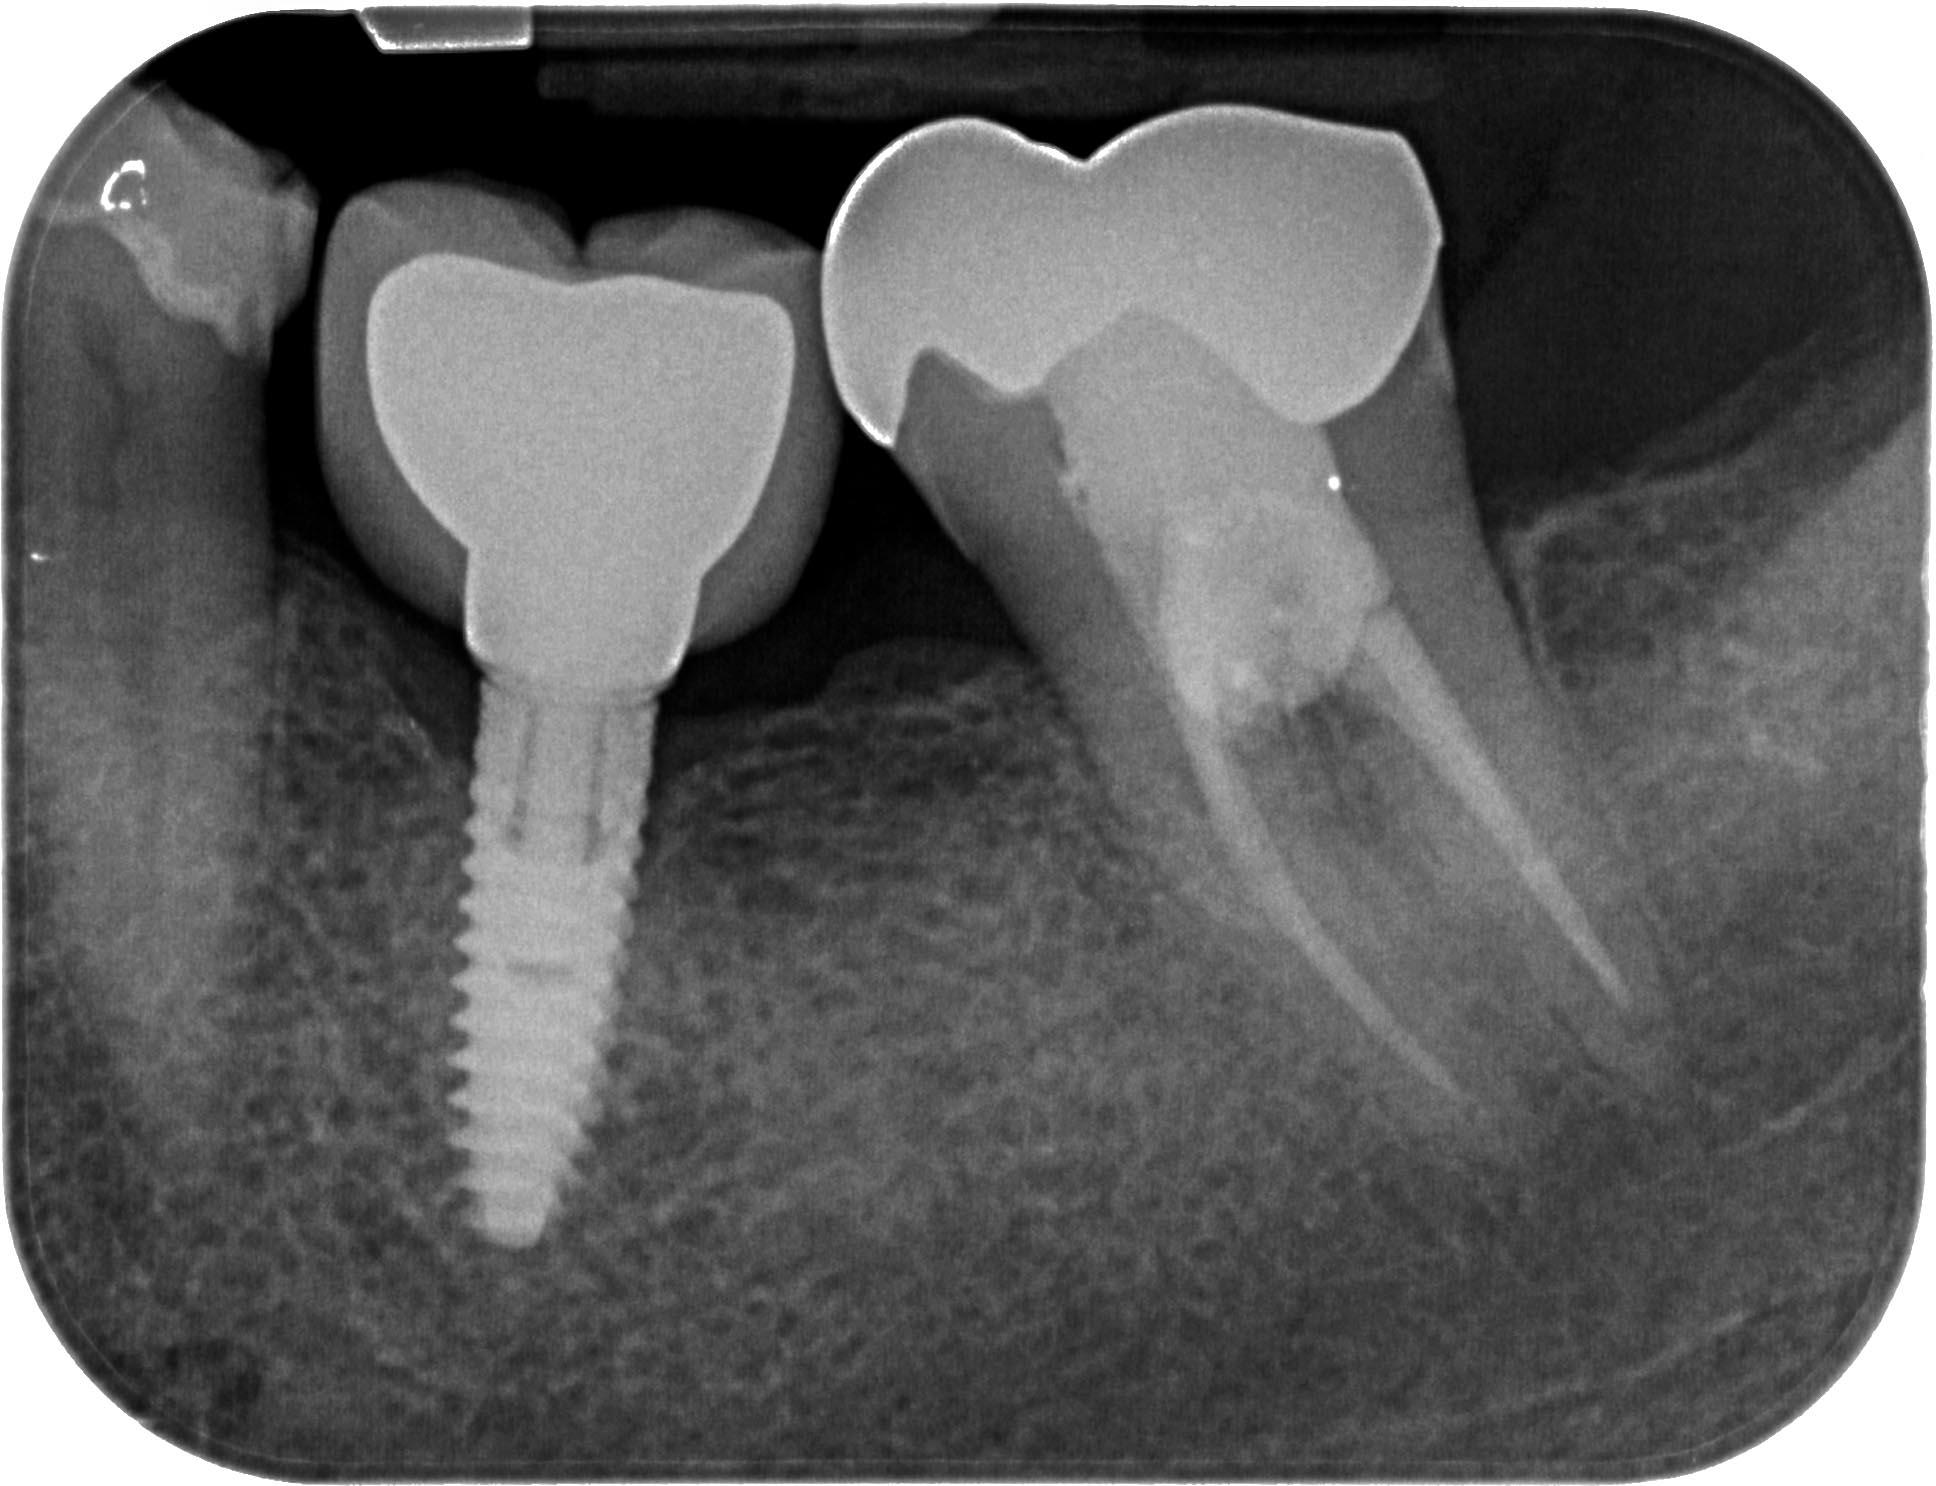

Distal-4 Veröffentlicht 16. Mai 2016 am 1936 × 1486 in Starker distaler Knocheneinbruch – Lohnt der Versuch eines Zahnerhaltes ? Zahn 37 19 Monate post WF Mai 2016